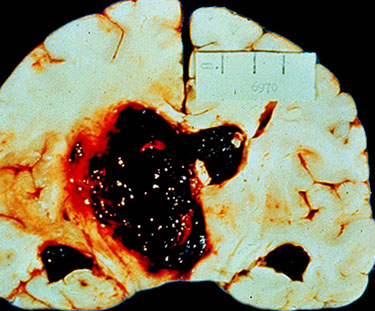

Hypertensive strokes, also hemorrhagic, usually occur in the basa ganglia

Gross:  acute cerebral hemorrhage of the deep nuclei, cerebellum, or pons; lacunar infarcts: basal ganglia, periventricular white matter, or both

Micro: Acute hemorrhage with acute blood clot and dissection through CNS tissue, sometimes with intraventricular or subarachnoid extension

-- Lacunar lesions may represent foci of ischemic infarction or widened perivascular spaces seen in the basal ganglia

-- Blood vessel: Hyaline arteriolosclerosis, lipohyalinosis, Charcot-Bouchard aneurysms (rarely observed in routine practice)

DDx: Lobar hemorrhage in patients with cerebral amyloid angiopathy or coagulopathies may mimic hypertensive hemorrhage.